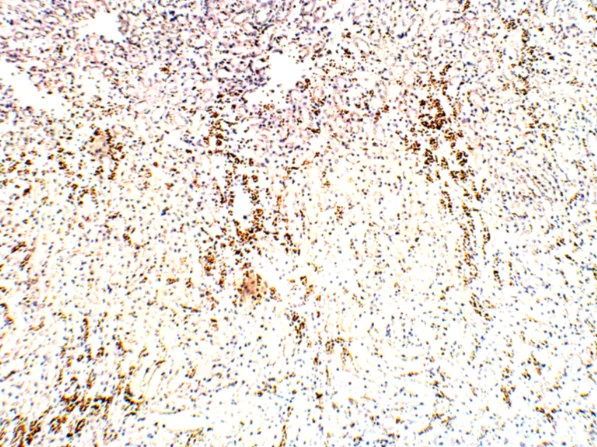

Immunohistochemistry (Formalin/PFA-fixed paraffin-embedded sections) - Anti-FOXP3 antibody (AB75763)

Immunohistochemistry (Formalin/PFA-fixed paraffin-embedded sections) of Rat kidney tissue staining FOXP3 using ab75763 at 1/100. DAB staining (brown) Hematoxylin QS counterstain (blue).